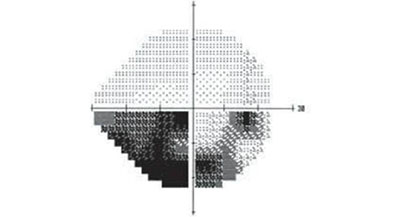

青光眼急性發(fā)作時(shí),由于角膜水腫,同時(shí)瞳孔散大后虹膜不太容易觀察到,患者的眼球呈現(xiàn)的就是這樣的外觀:角膜呈灰綠色,有點(diǎn)放光。所以青光眼三個(gè)字,描繪的是青光眼急性發(fā)作時(shí)眼睛的外觀。

閉上左眼,只睜開右眼。如果感覺右眼看到的范圍里有一部分看不到東西,就證明你的視野出現(xiàn)缺損,同樣的,閉上右眼,只睜開左眼,可以測試左眼有沒有視野缺損。如果出現(xiàn)視野缺損,一定要及時(shí)到醫(yī)院進(jìn)一步檢查、治療,防止青光眼一點(diǎn)點(diǎn)“吃掉”眼睛的視野,導(dǎo)致眼睛完全失明。